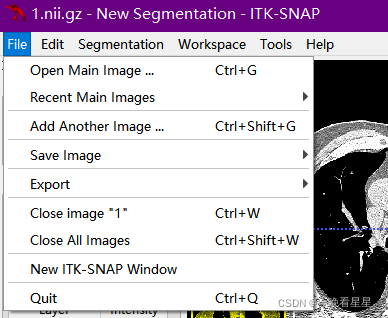

1.2 File菜单

- 常用的打开功能,这里不多介绍,会使用基本的软件路径打开即可

- 重点介绍ITK-Snap特有的功能

Add Another Image可以进行不同DICOM文件的融合,比如不同段的CT扫描图像save Image -> main Image可以对文件进行另存export导出文件:

Image Slice单对切面的导出,导出的格式为png, 不包含标注的图像Screenshot / Screenshot Series将图片导出为截图的格式,包含了图片的标注信息。与导出切片不同,导出的截图与图像在软件中的显示是一样的,常用于一些图像的说明